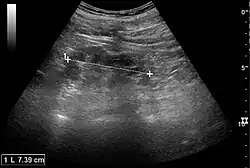

Acute pyelonephritis with increased cortical echogenicity and blurred delineation of the upper pole[20]

Ultrasound findings that indicate pyelonephritis are enlargement of the kidney, edema in the renal sinus or parenchyma, bleeding, loss of corticomedullary differentiation, abscess formation, or an areas of poor blood flow on doppler ultrasound.[21] However, ultrasound findings are seen in only 20–24% of people with pyelonephritis.[21]